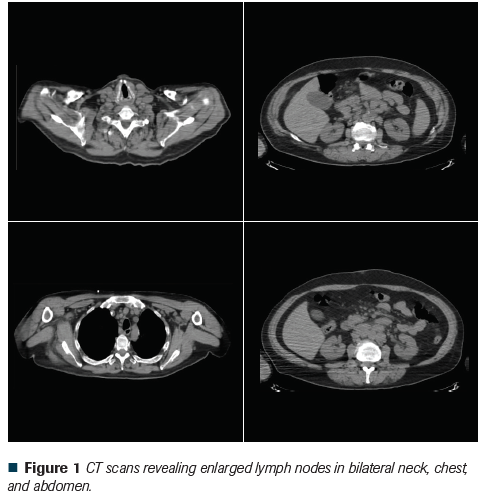

Figure 1 CT scans revealing enlarged lymph nodes in bilateral neck, chest, and abdomen.

In 2018, he presented with anorexia, vomiting, mild mental confusion, and weight loss. Further work up revealed hypercalcemia (Ca: 17.6 mg/dL, normal: 8.1-10.1 mg/dL), elevated WBC with lymphocytosis (WBC: 19.7 per cubic mL, with 81% lymphocytes), mild anemia (hemoglobin: 12.4 g/dL) and thrombocytopenia (platelet count 86,000 per cubic mL). Serum level of parathyroid hormone (PTH) was suppressed (PTH intact: 10 pg/mL, normal 12-65 pg/mL). The serum level of PTH-related peptide (PTHrP) was slightly elevated (PTHrP: 2.5 pmol/L, normal <2 pmol/L). The serum levels of vitamin D (25-hydroxyvitamin D: 25.6 ng/dL, normal: 30-61 ng/dL) and 1,25-dihydroxyvitamin D (1,25-dihydroxyvitamin D: 8.4 pg/mL, normal: 19.9-79.3 pg/mL) were both low. Serum thyroid-stimulating hormone and thyroxin levels were normal. Ultrasound of thyroid and parathyroid glands and a bone scan were normal. Computed tomography (CT) scans revealed enlarged lymph nodes in the bilateral neck, supraclavicular, mediastinum, hilum, central mesentery, aortocaval, and bilateral groin areas (Figure 1).